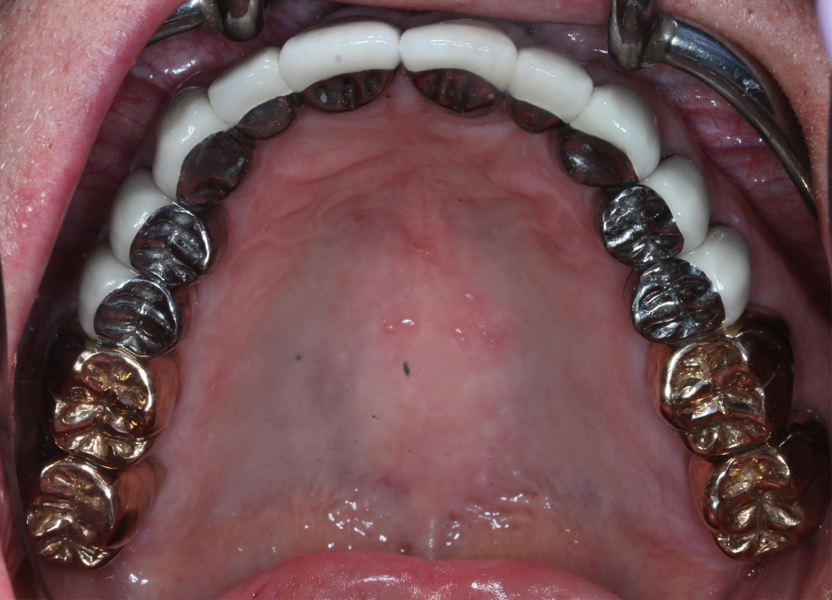

Full mouth of Crowns!

We took a patient that had several worn teeth and restored them back to shape with crowns. We chose metal crowns for this patient because he was a heavy grinder and metal crowns have been shown to be more beneficial than ceramic crowns for patients that grind their teeth.